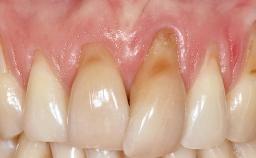

A 30-year-old woman was referred by her general dentist for evaluation of an esthetic complication related to previous implant treatment for congenitally missing maxillary lateral incisors. The patient’s chief complaint was the inadequate esthetic appearance of her smile. The case demonstrates the use of a combined approach to achieve optimal results. Two different flap designs - a tunnel technique and a coronally advanced flap - are employed based on the surgical objectives for the affected site.

Soft Tissue Grafting Yes

Soft Tissue Anatomy Intact Defective

Soft Tissue Contour and Volume Slightly compromised